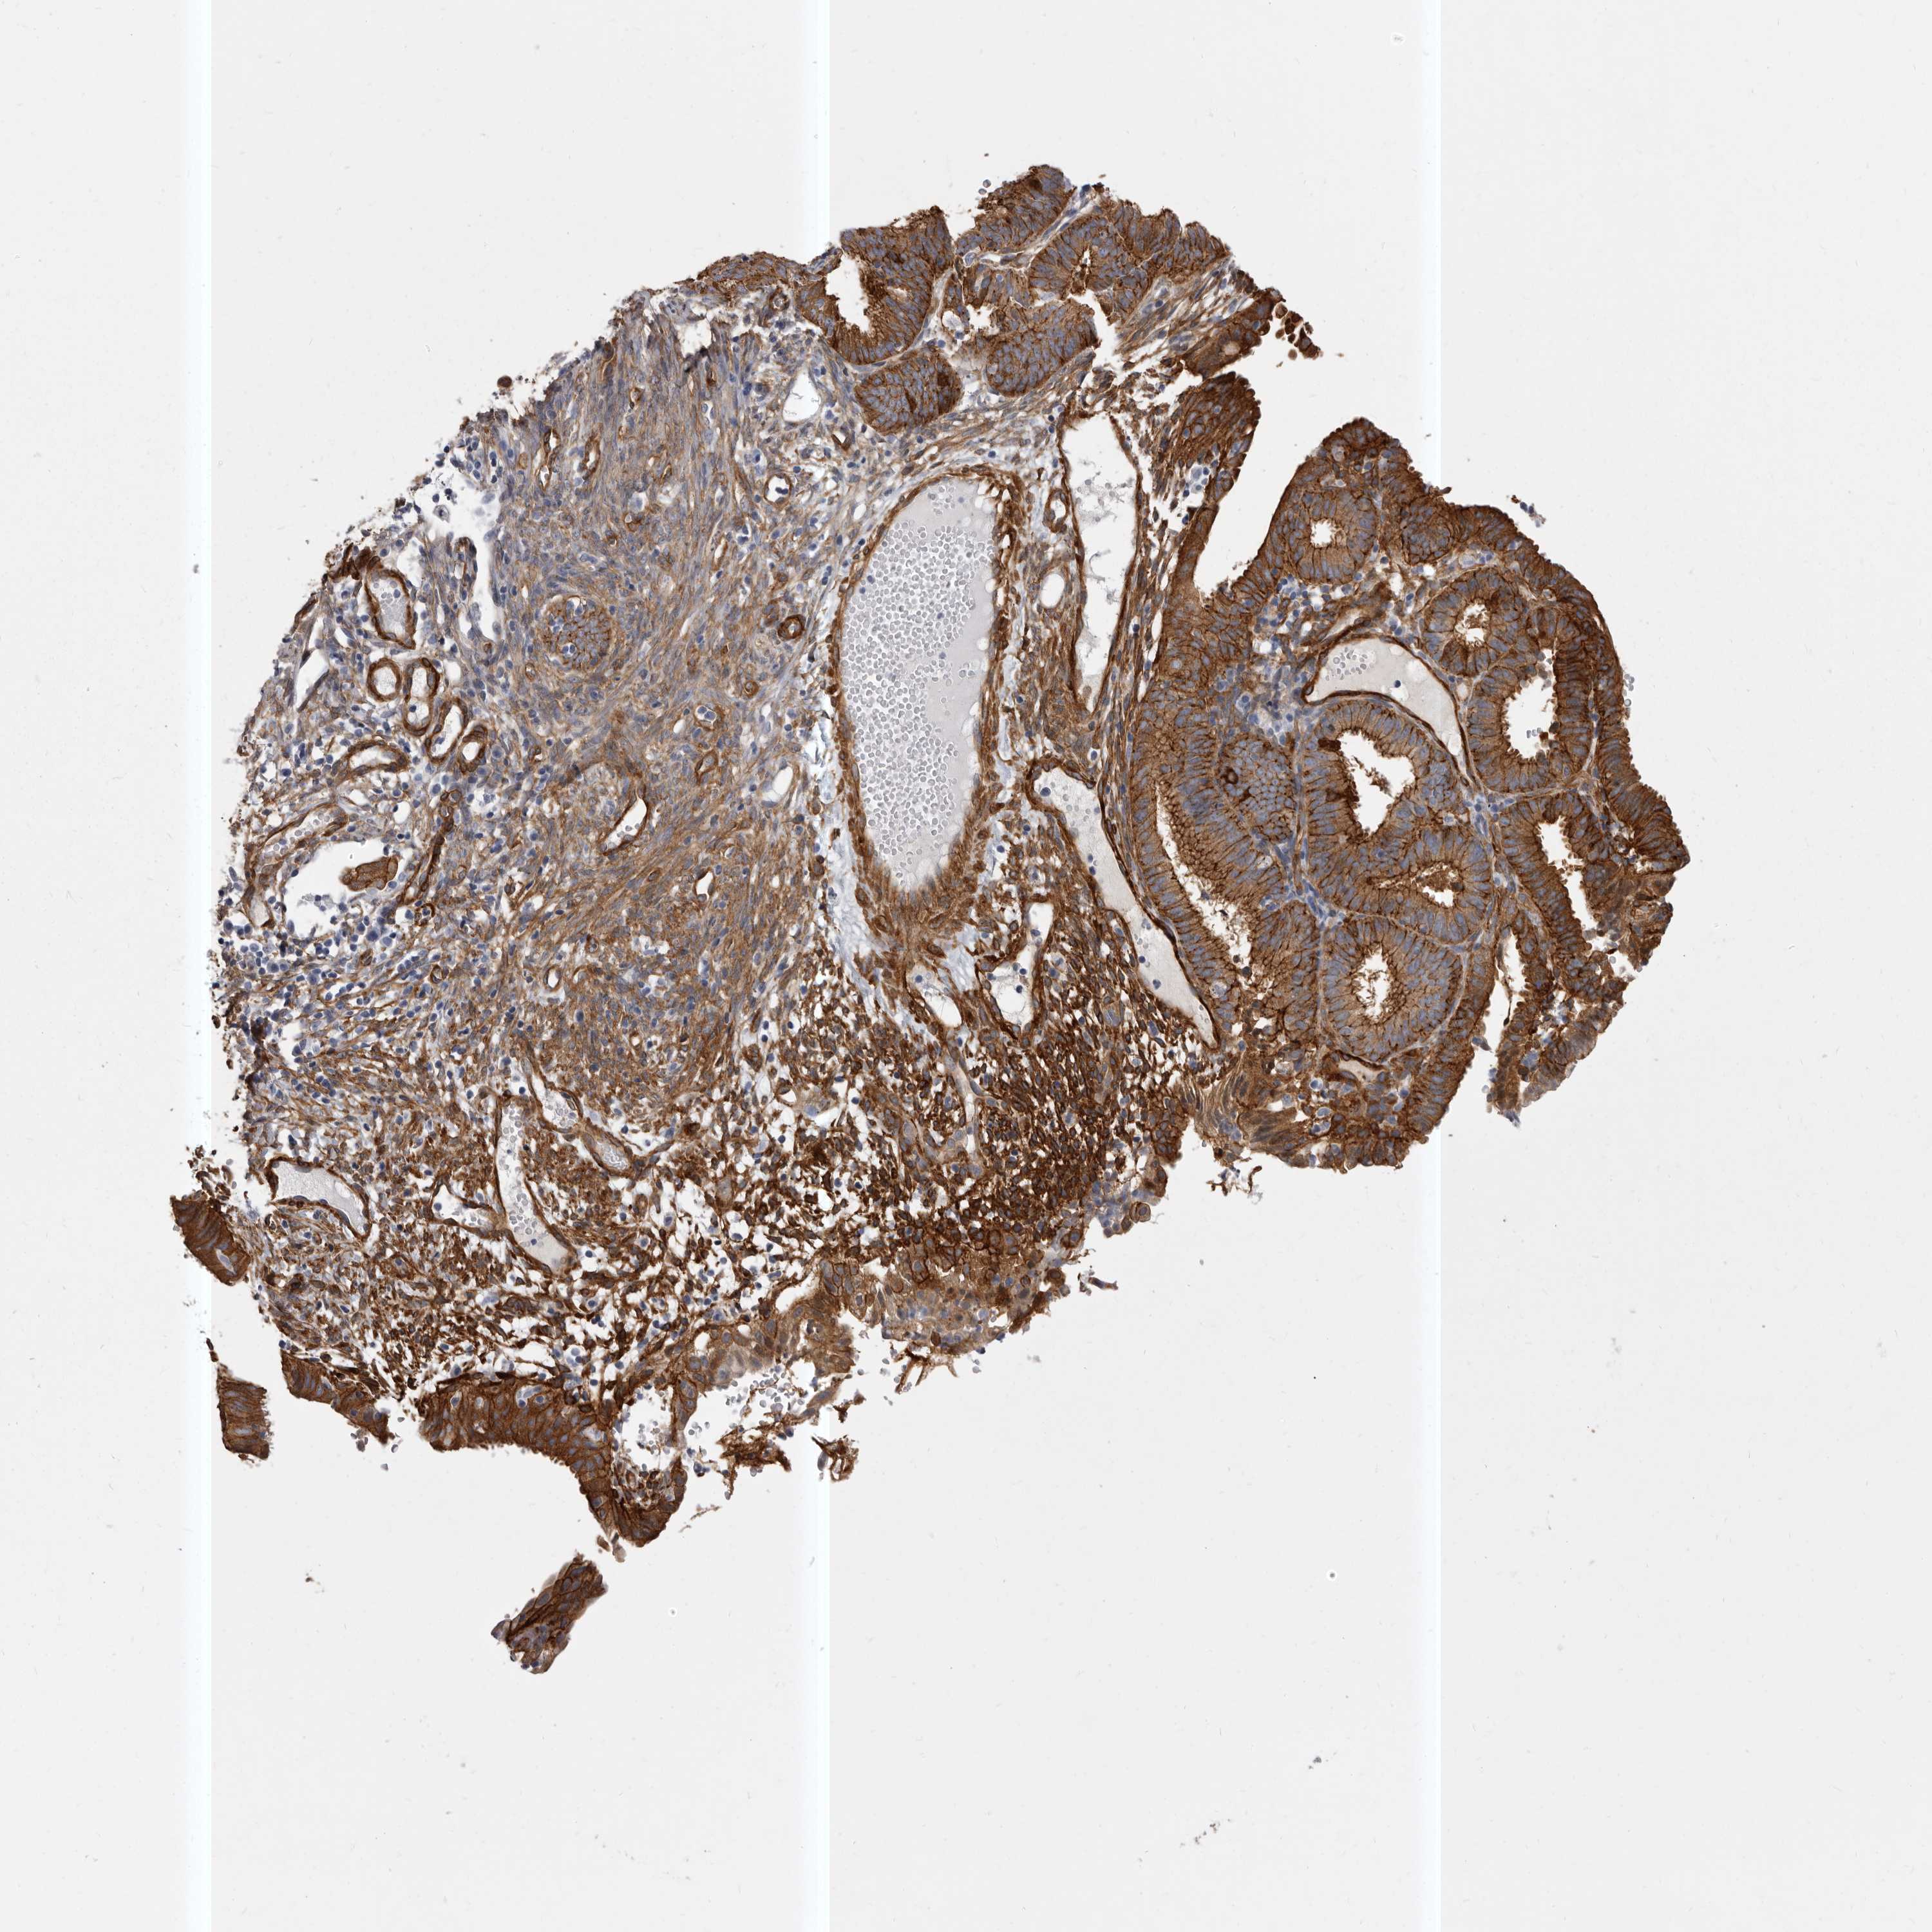

ENDOMETRIAL CANCER - Protein expressioni

A mouse-over function shows sample information and annotation data. Click on an image to view it in a full screen mode. Samples can be filtered based on level of antibody staining by selecting one or several of the following categories: high, medium, low and not detected. The assay and annotation is described here.

Note that samples used for immunohistochemistry by the Human Protein Atlas do not correspond to samples in the TCGA dataset.

Antibody stainingi

Antibody staining in the annotated cell types in the current human tissue is reported as not detected, low, medium, or high, based on conventional immunohistochemistry profiling in selected tissues. This score is based on the combination of the staining intensity and fraction of stained cells.

Each image is clickable and will lead to virtual microscopy that enables deeper exploration of all samples and also displays staining intensity scores, fraction scores and subcellular localization as well as patient and tissue information for each sample.

Antibody HPA028448

Antibody HPA028696

Staining

High

Medium

Low

Not detected

Intensity

Strong

Moderate

Weak

Negative

Quantity

>75%

75%-25%

<25%

None

Location

Nuclear

Cytoplasmic/membranous

Cytoplasmic/membranous,nuclear

Adenocarcinoma, NOS

Adenocarcinoma, metastatic, NOS